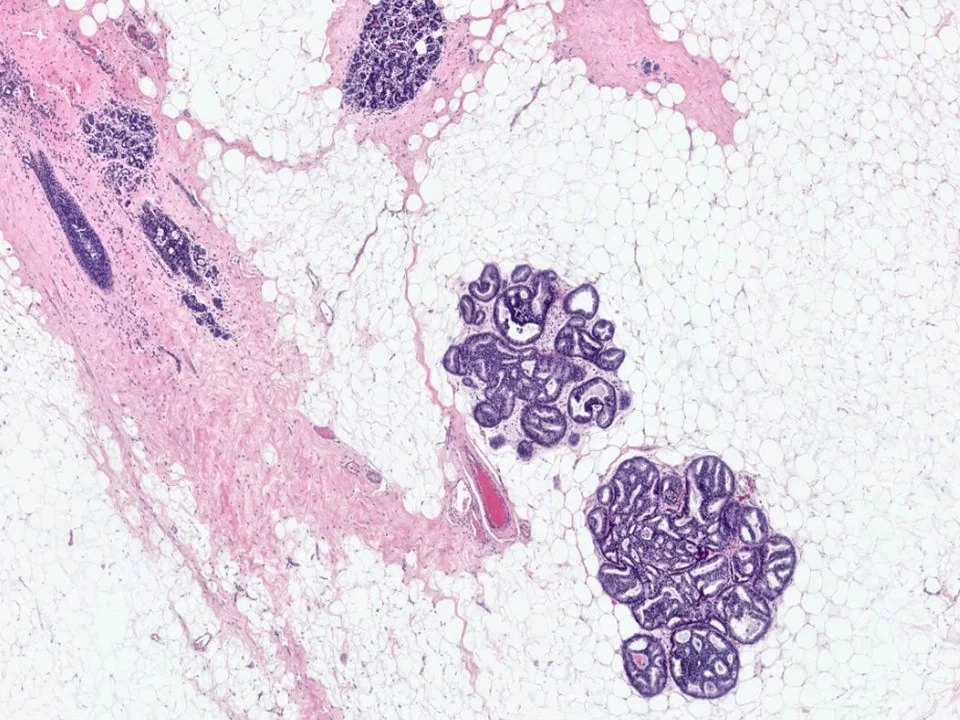

Microglandular adenosis is characterized by an infiltrative, nonlobulocentric proliferation of relatively uniform, small glands within the stroma and adipose tissue.

Microglandular Adenosis

Microglandular adenosis is composed of small round glands that are lined by a single layer of flat-to-cuboidal epithelial cells. The glands lack an outer myoepithelial cell layer. They often have an eosinophilic, PAS+ Diastase resistant secretory material within the lumina.